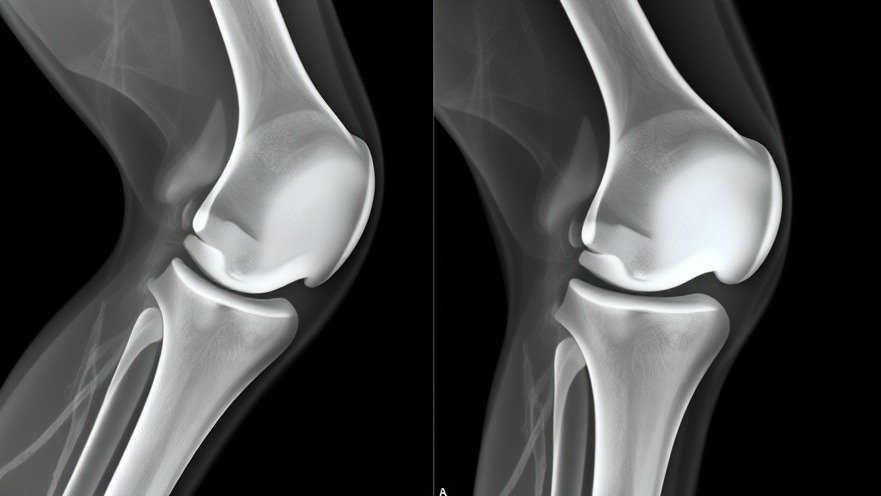

The young girl’s journey underscores what many local medical practices encounter. Initially relying on conservative treatments like medications and physical therapy proved insufficient due to persistent symptoms. This highlights the importance of thorough evaluations for primary care doctors. The initial X-rays didn't reveal significant degenerative changes, yet the MRI pointed towards a serious condition requiring surgical intervention.